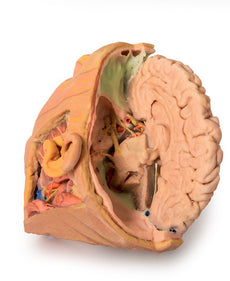

Within the endocranial cavity, the sectioned brain is slightly off the midagittal

plane, such that neither the superior sagittal sinus nor the third ventricle are

clearly defined - but the lateral ventricle is open and part of the fourth ventricle

is preserved between the pons and cerebellum. The gyri and sulci of the

cerebrum are not well separated, but the cingulate gyrus and corpus callosum

can be separated. Cross-sectioned views of the optic tract, pituitary gland,

superior and inferior colliculi, superior cerebellar peduncle, and transition

between the medulla oblongata and spinal cord are all visible. The tentorium

cerebelli and confluence/transverse sinus is positioned between the

cerebellar hemisphere and occipital lobe. Small portions of the posterior

inferior cerebellar artery, vertebral arteries, basilar artery, and posterior

cerebral and anterior cerebral arteries are visible in section.